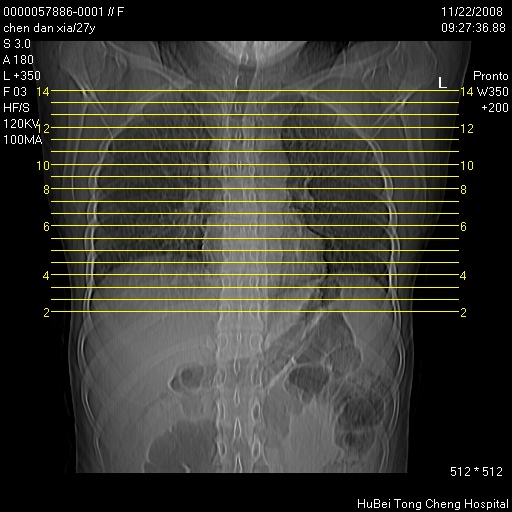

标题: CT16752:F,27Y。发热咳嗽20余天,伴盗汗。 [打印本页]

标题: CT16752:F,27Y。发热咳嗽20余天,伴盗汗。